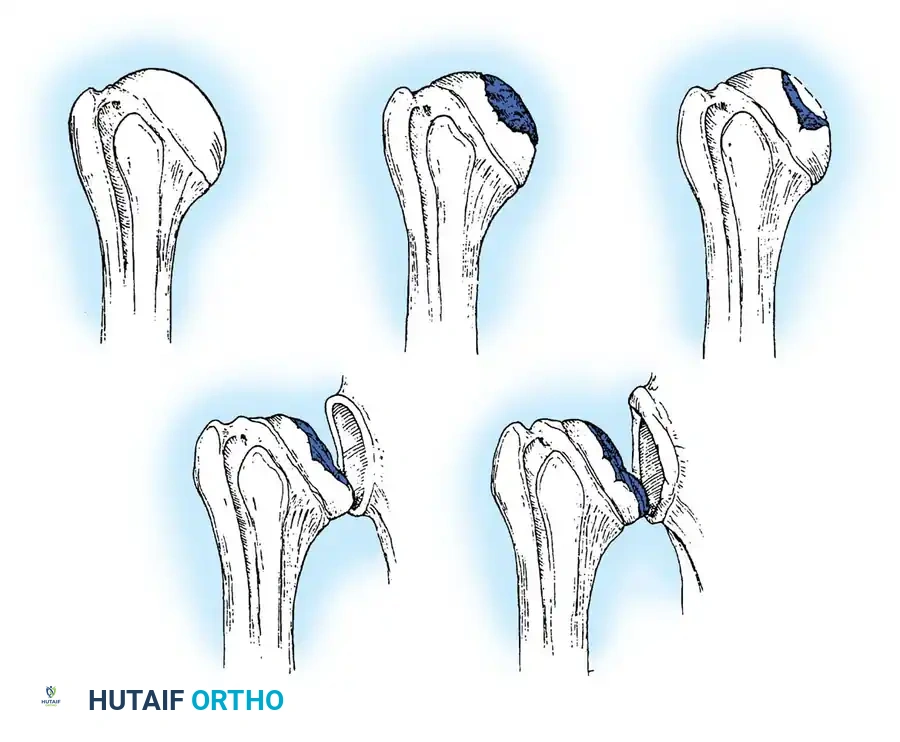

Indications for Reverse TSA (rTSA):

* Rotator cuff tear arthropathy (CTA).

* Massive, irreparable rotator cuff tears with pseudoparalysis.

* Complex 3- and 4-part proximal humerus fractures in the elderly.

* Revision of failed anatomical TSA.

Standard radiographs must include a true anteroposterior (Grashey), axillary lateral, and scapular Y view. A non-contrast CT scan is mandatory for evaluating glenoid bone stock, version, and morphology (utilizing the Walch classification for posterior wear).

Reverse Total Shoulder Arthroplasty (rTSA)

The rTSA fundamentally alters shoulder biomechanics. By medializing and distalizing the center of rotation, it increases the deltoid moment arm and recruits more anterior and posterior deltoid fibers for elevation, bypassing the need for a functional rotator cuff.

Surgical Nuances for rTSA:

* Glenoid Baseplate: Must be positioned inferiorly on the glenoid to avoid scapular notching. A slight inferior tilt (10 degrees) is often utilized.

* Glenosphere: Typically 36 mm or 42 mm. Larger spheres increase stability and range of motion but may increase the risk of notching.

* Humeral Stem: Often placed in 0 to 20 degrees of retroversion.

- Scapular Notching (rTSA): Mechanical impingement of the humeral component against the inferior scapular neck during adduction. Minimized by inferior placement and tilt of the glenosphere.